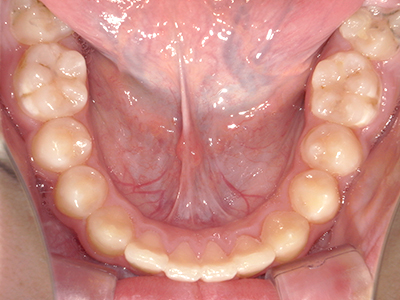

歯並びの相談に来られるお子様は、口呼吸をしているケースが多く、これが歯並びに大きな影響を与えています。

↓ - 頬の圧力が上の歯列にかかりやすくなる

↓ - 上あごが狭くなる

↓ - 下あごが狭くなる・下あごの位置が悪くなる

↓ - さまざまな不正咬合が生じる

ないき歯科クリニックでは、上あごの成長不足を補い、鼻呼吸を獲得しつつ歯列を整え、将来のお口をより健康な状態にすることをゴールに定める矯正治療をおこなっています。